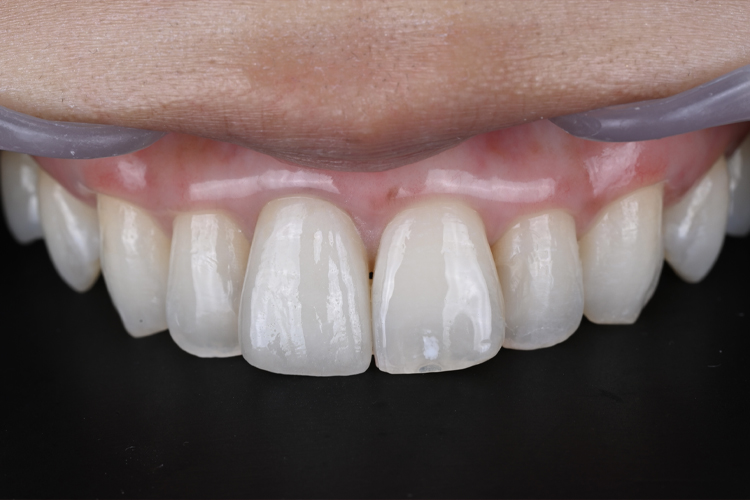

精密印象時

歯肉に炎症がないことを確認し、

問題なければ精密印象へ。

Set時

左右非対称の改善と色調を自然な白さにすることで、全体的に馴染みました。

また、歯肉もガムピーリングを行ったことで健康的なピンクになり、さらに美しい仕上がりになりました。